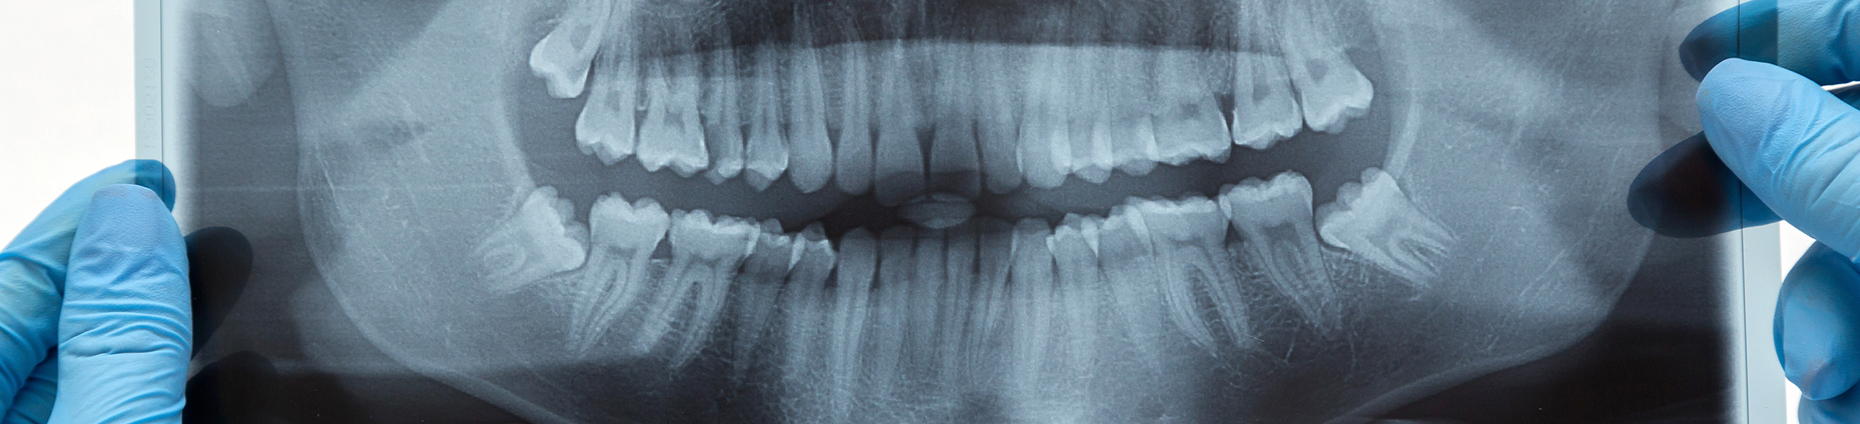

Hochwertige Zahnmedizin auf Basis moderner Technik

In unserer Zahnarztpraxis in Sprockhövel können wir Behandlungen durch digitale Prozesse, minimalinvasives Vorgehen und moderne Technik deutlich vereinfachen. Für Patienten bedeutet dies weniger Belastung und schnellere Wundheilung.